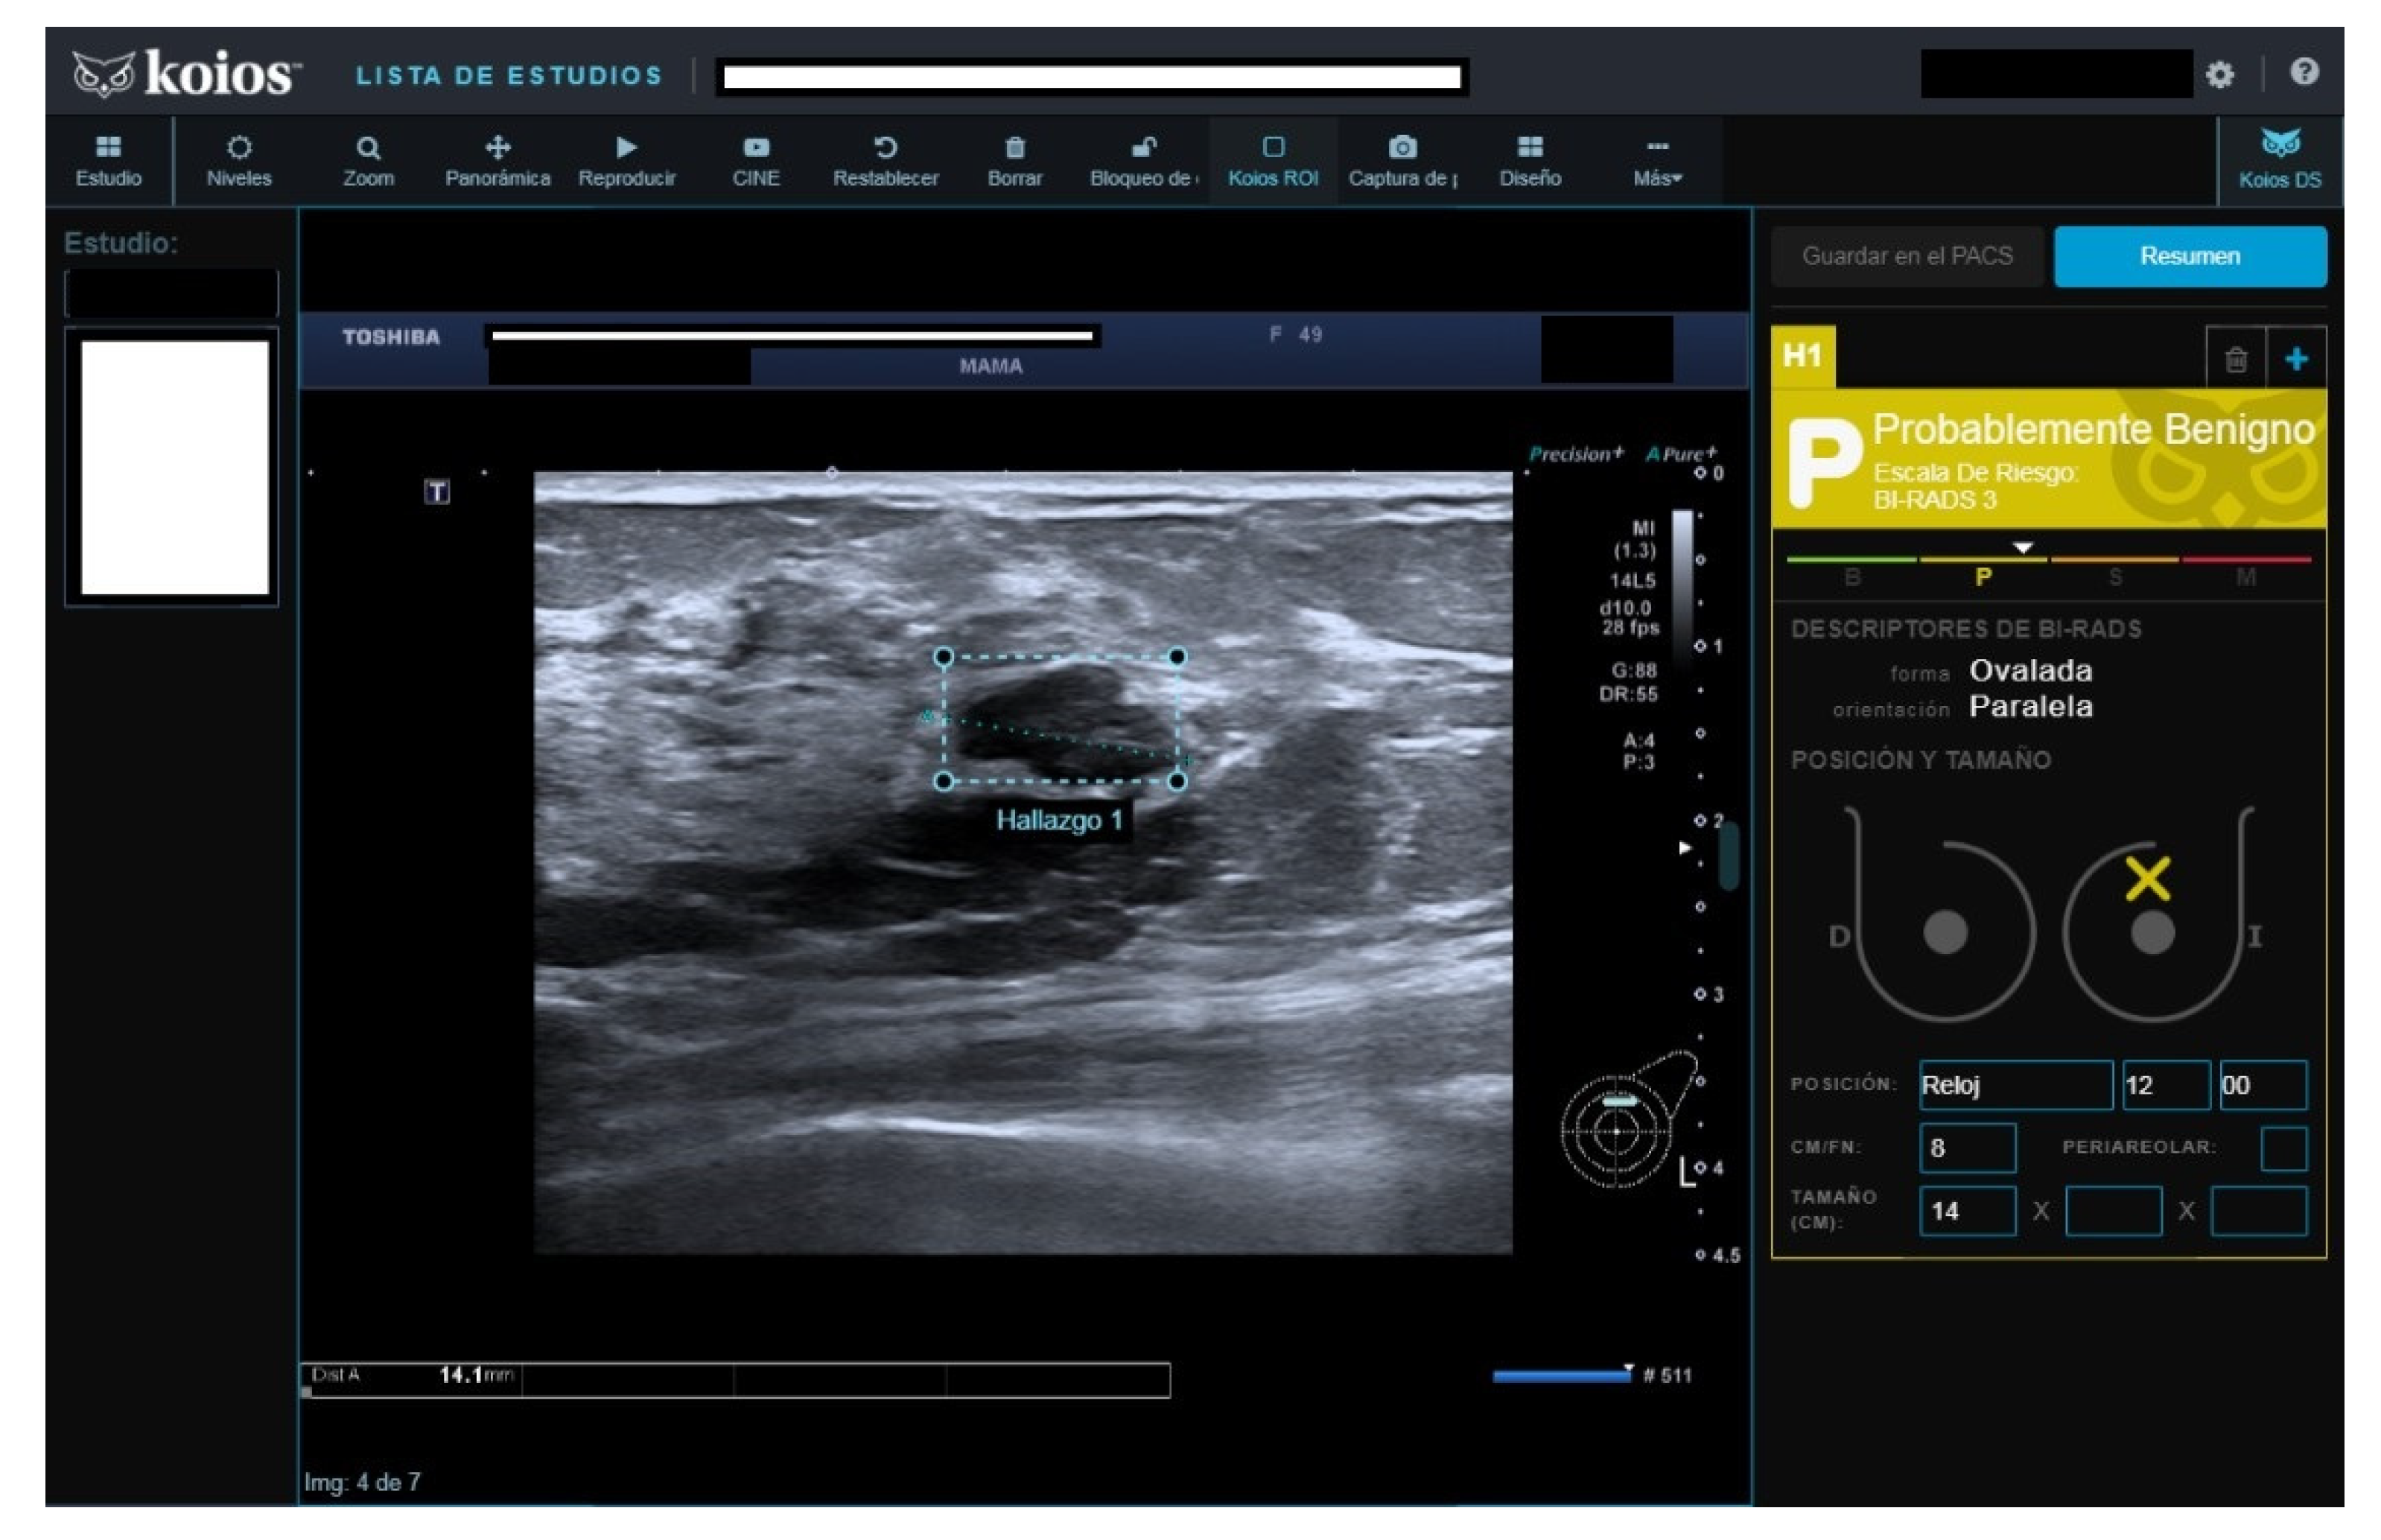

Figure 4.

Nodule rated B3 by reader (no Doppler), KSS by KOIOS. Cytology reported grade 1 carcinoma. Biopsy confirmed invasive carcinoma.